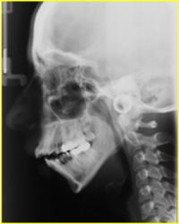

II Classe Ipodivergente morso profondo

Casi Clinici pre - post Chirurgiia Ortognatodontica

casi trattati chirurgicamente dal Prof. Aldo Bruno Giannì